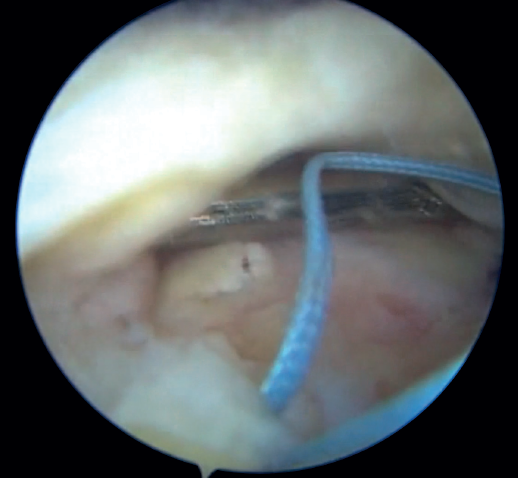

The magnetic resonance imaging (MRI) study prior to surgery allows us to assess the percentage of rupture according to the degrees of tendon retraction established in the Patte classification (Figure 1).